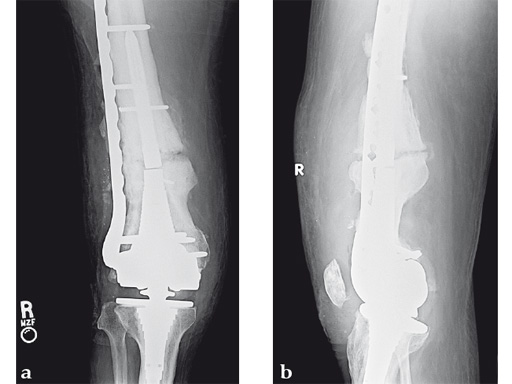

Case 3: A 53-year-old man with hypotestosteronism, low vitamin D levels, and calcium metabolism problems. Recalcitrant atrophic nonunion of his distal femur after three surgical attempts with an extension and flexion contracture of his knee.

The VA-LCP Curved Condylar Plate was used to avoid previous enlarged screw holes and allow for stable fixation in the patient's osteoporotic distal segment. Secondary to his metabolic and mechanical problems, the decision was made to proceed with an endosteal implant and place interlocking screws through that implant from the VA-LCP Curved Condylar Plate. The combination of the retrograde/antegrade femoral nail and VA-LCP provides a very stable mechanical environment for the expected prolonged healing response.